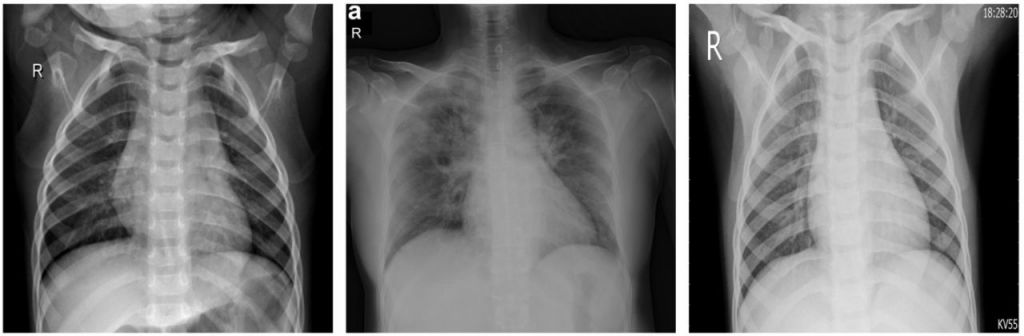

(왼쪽부터) 정상인, 코로나19 환자, 바이러스성 폐렴 환자의 폐 X레이 사진(사진제공=MDPI).

여기에는 X레이 기술이 동원된다. 특정인의 흉부 X레이 사진을 코로나19 환자, 건강한 사람, 바이러스성 폐렴 환자의 사진 약 3000장과 비교·판독하는 것이다. 이 AI 프로그램의 진단 정확도는 98%에 이르는 것으로 밝혀졌다.